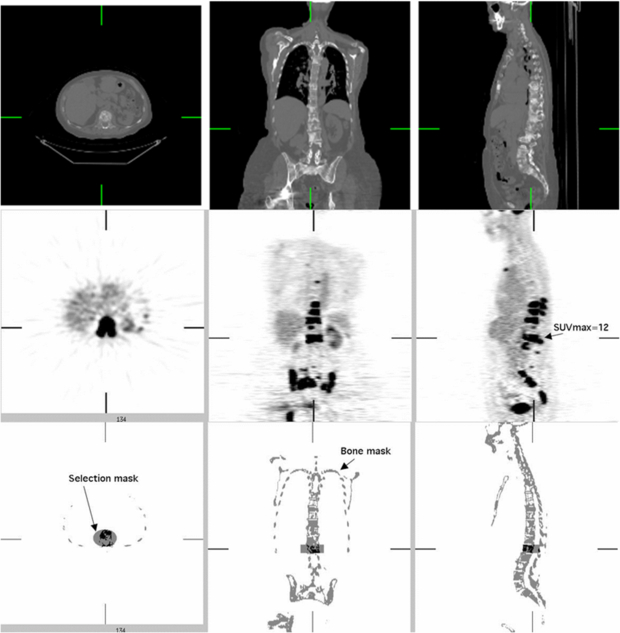

In the third experiment, we used CT and PET images from five patient exams with significant FDG uptake in bone tissue. Similar to experiment 2, we measured the bias of the FDG uptake due to simulated errors in attenuation correction. The experimental process is outlined in figure 6. Since patients were imaged only on the PET/CT scanner (figure 7 shows one of these studies), 511 keV PET TX images were not available. For these patient exams we used the measured LACCTAC and SUV images as the reference standards.

Standard imageFigure 7. Illustration of masking process used for one of the five PET/CT patient scans with significant FDG uptake in bone. Top: axial, sagittal and coronal views of 70 cm diameter FOV CT image. Middle: PET FDG images. Bottom: bone mask based on PET and CT images with one of the cylindrical selection masks used to isolate one vertebra for analysis.

Download figure:

Standard imageThe values used for comparison in each selected site corresponding to a bone metastasis were expressed in terms of maximum (SUVMAX) and mean value (SUV75) in a contiguous volume of interest (VOI) covering all voxels with SUVs at least 75% of SUVMAX5. We used 12 VOIs selected from the five studies of pre-treatment breast cancer patients with extensive bone metastases in the thoracic spine, lumbar spine and pelvis.

The VOIs were obtained by the following procedure. First a bone mask image was segmented by thresholding the CT image after resampling and filtering to match the PET image resolution. Cylindrical VOIs were then manually defined to select specific bony areas with elevated FDG uptake. The tumor volume values were then obtained by including the voxels in the intersection of both the cylindrical VOIs and the bone image mask with values higher than 75% of SUVMAX (figure 7). We measured the dependence of the error in SUVCTAC images as a function of the estimated SUVMAX values, as well as the dependence on introduced errors in LACCTAC (we tested errors in LACCTAC of 2%, 4%, 6% and 8%).

The estimated bias in SUVMAX as a function of 'true' SUVMAX is presented in figure 8(A) for each LACCTAC bias (−2%, −4%, −6% and −8%) introduced to the 12 lesions from five patient emission images. Here 'true' SUVMAX was found using the default LACCTAC because LACTX were not available for these images.

Standard imageWhen the results are averaged for all SUV values (figure 8(B)) there is an approximate error in SUVMAX of 1% for each percentage error in LACCTAC, which is in agreement with our previously reported results for soft tissue (Kinahan et al 2006). The variability in the SUV bias also increased approximately linearly with the error in LACCTAC (figure 8(B)). There was a weak inverse dependence of bias in SUVMAX on the true SUV value (figure 8(A)). Similar results to those described above for SUVMAX were found for SUV75.

While the results from tables 3 and 4 determine the impact of errors in LACCTAC on PET SUVs, they do not take into account the important effects of the location and size of attenuating material in patient images. To include these effects and perform a more extended sensitivity analysis, we used five additional patient images with significant FDG uptake in bone lesions (e.g. figure 7). This allowed estimation of the error in FDG uptake as a function of the error in the CTAC and nominal SUV uptake as shown in figure 8(A). From figure 8(B) we see that the per cent error in PET SUVMAX is roughly proportional to the per cent error in LACCTAC. Very similar results were found for SUV75 (data not shown). These results are consistent with our previous results for soft tissues (Kinahan et al 2006). As expected, the variability of SUV measurements increased with increasing error in LAC factors because of the propagation of error from multiplicative terms.

Based on figure 8(B), with a typical error in LACCTAC of up to −3.1% at 140 kVp and up to −6.8% at 120 kVp, we would thus expect an SUVMAX error of approximately −3.1% and −6.8% at 140 and 120 kVp. This represents a range for PET/CT imaging parameters on clinical scanners using the tri-linear transform method described above (figure 1 and table 1).